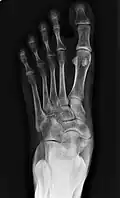

From left to right: Type 1, 2 and 3